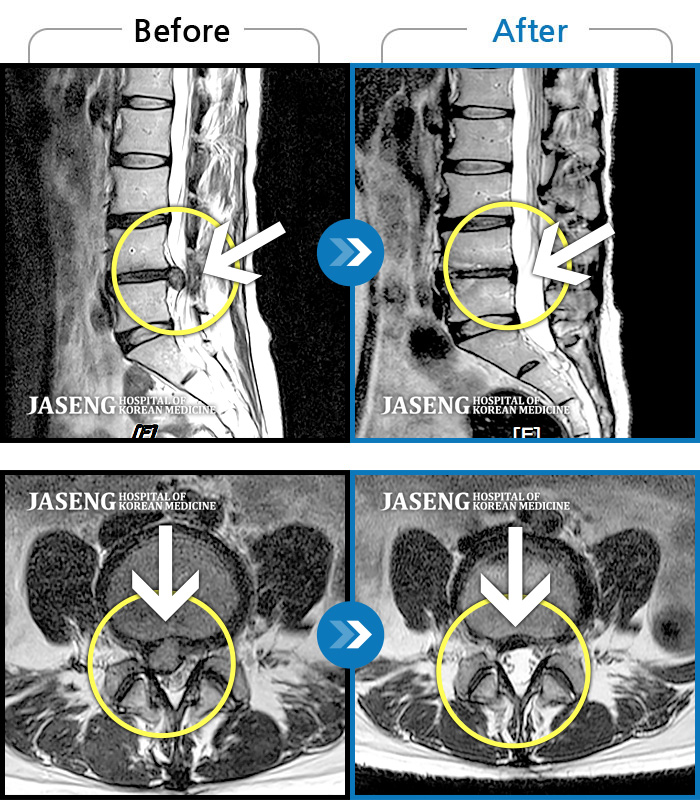

40대 초반 여성 환자인데요,, 처음 선생님 뵈었을 때에 1번,4,5번허리디스크 증상도 증상이지만,

본인 나이에 비해서 10~15년정도 퇴행이 많이 되어있어서 전체적으로 관리가 많이 필요하다고 설명해주셨구요,,

그당시 원장님진료실에서 보았던 저의 엠알아이사진이 아직도 생생히 기억이 납니다 ^^

뼈부분의 색이 왜저렇게 검냐고 여쭈어 보았더니, 말씀주신데로 "퇴행이"많이 되어서 그렇다고 설명해주시면서,,